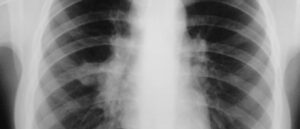

Гемангиома легкого

Гемангиома — часто встречаемое сосудистое образование в главном органе дыхания. Гемангиома легких — редкое образование в виде опухоли, которое в 99% случаев доброкачественное и чаще, поражающее нижние отделы органа. Патология в легком представляет собой скопление анастомозирующих сосудов крови, размером 0,4—8,5 см в диаметре (средний показатель — 2,8 см). Чаще формируется у детей после 6—7-ми лет …